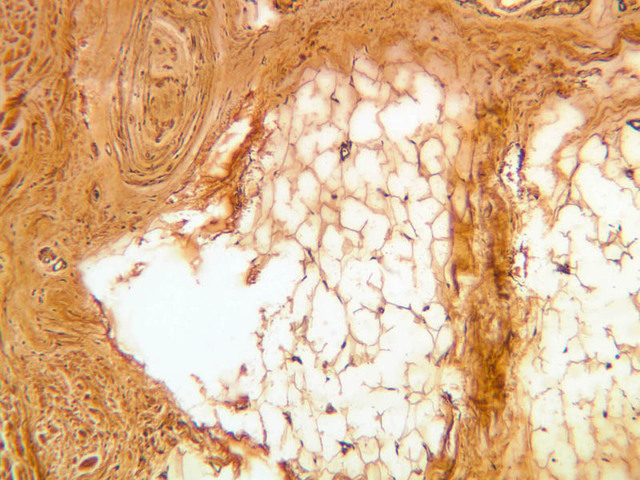

The hypodermis (subcutaneous fat) is located deep to the dermis (A-57, [2.5x-labeled, 10x, 20x, 40x]). This layer typically consists of loose connective tissue and adipose tissue. In the Gross Anatomy lab, this layer is referred to as the superficial fascia.

Deep pressure receptors known as Pacinian corpuscles also occur in the skin, as well as other sites (A-57 [2.5x-labeled, 10x, 20x, 40x-labeled] [2.5x, 10x, 20x, 40x-labeled]; A-50 [2.5x, 10x, 20x, 40x]). The sectioned appearance of the Pacinian corpuscle resembles a slice of onion, consisting of numerous concentric layers of tissue. Nerve endings generally thought to be responsible for pain sensation occur as bare fibers within the epithelial layers of skin epidermis, but these are not apparent in routinely stained sections (A-57, fingertip, Sevier Ag [10x, 20x, 40x] [10x, 20x, 40x] [20x, 40x] [20x, 40x]).